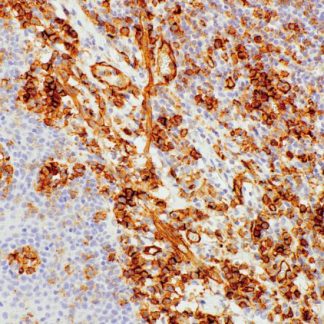

The GCDFP-15 (Gross Cystic Disease Fluid Protein-15) Antibody is a highly specific

immunohistochemical marker used to identify apocrine-differentiated breast carcinomas.

In pathology, GCDFP-15 shows strong cytoplasmic staining in breast adenocarcinomas.

Meanwhile, it is usually negative in lung, colorectal, and mesothelial tumors.

- Clear brown cytoplasmic staining in positive cells